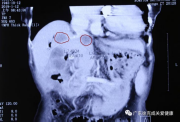

1月12日胆囊原发病灶(红圈指示)

11月27日肝转移灶(红圈指示)

1月12日肝转移灶(红圈指示)